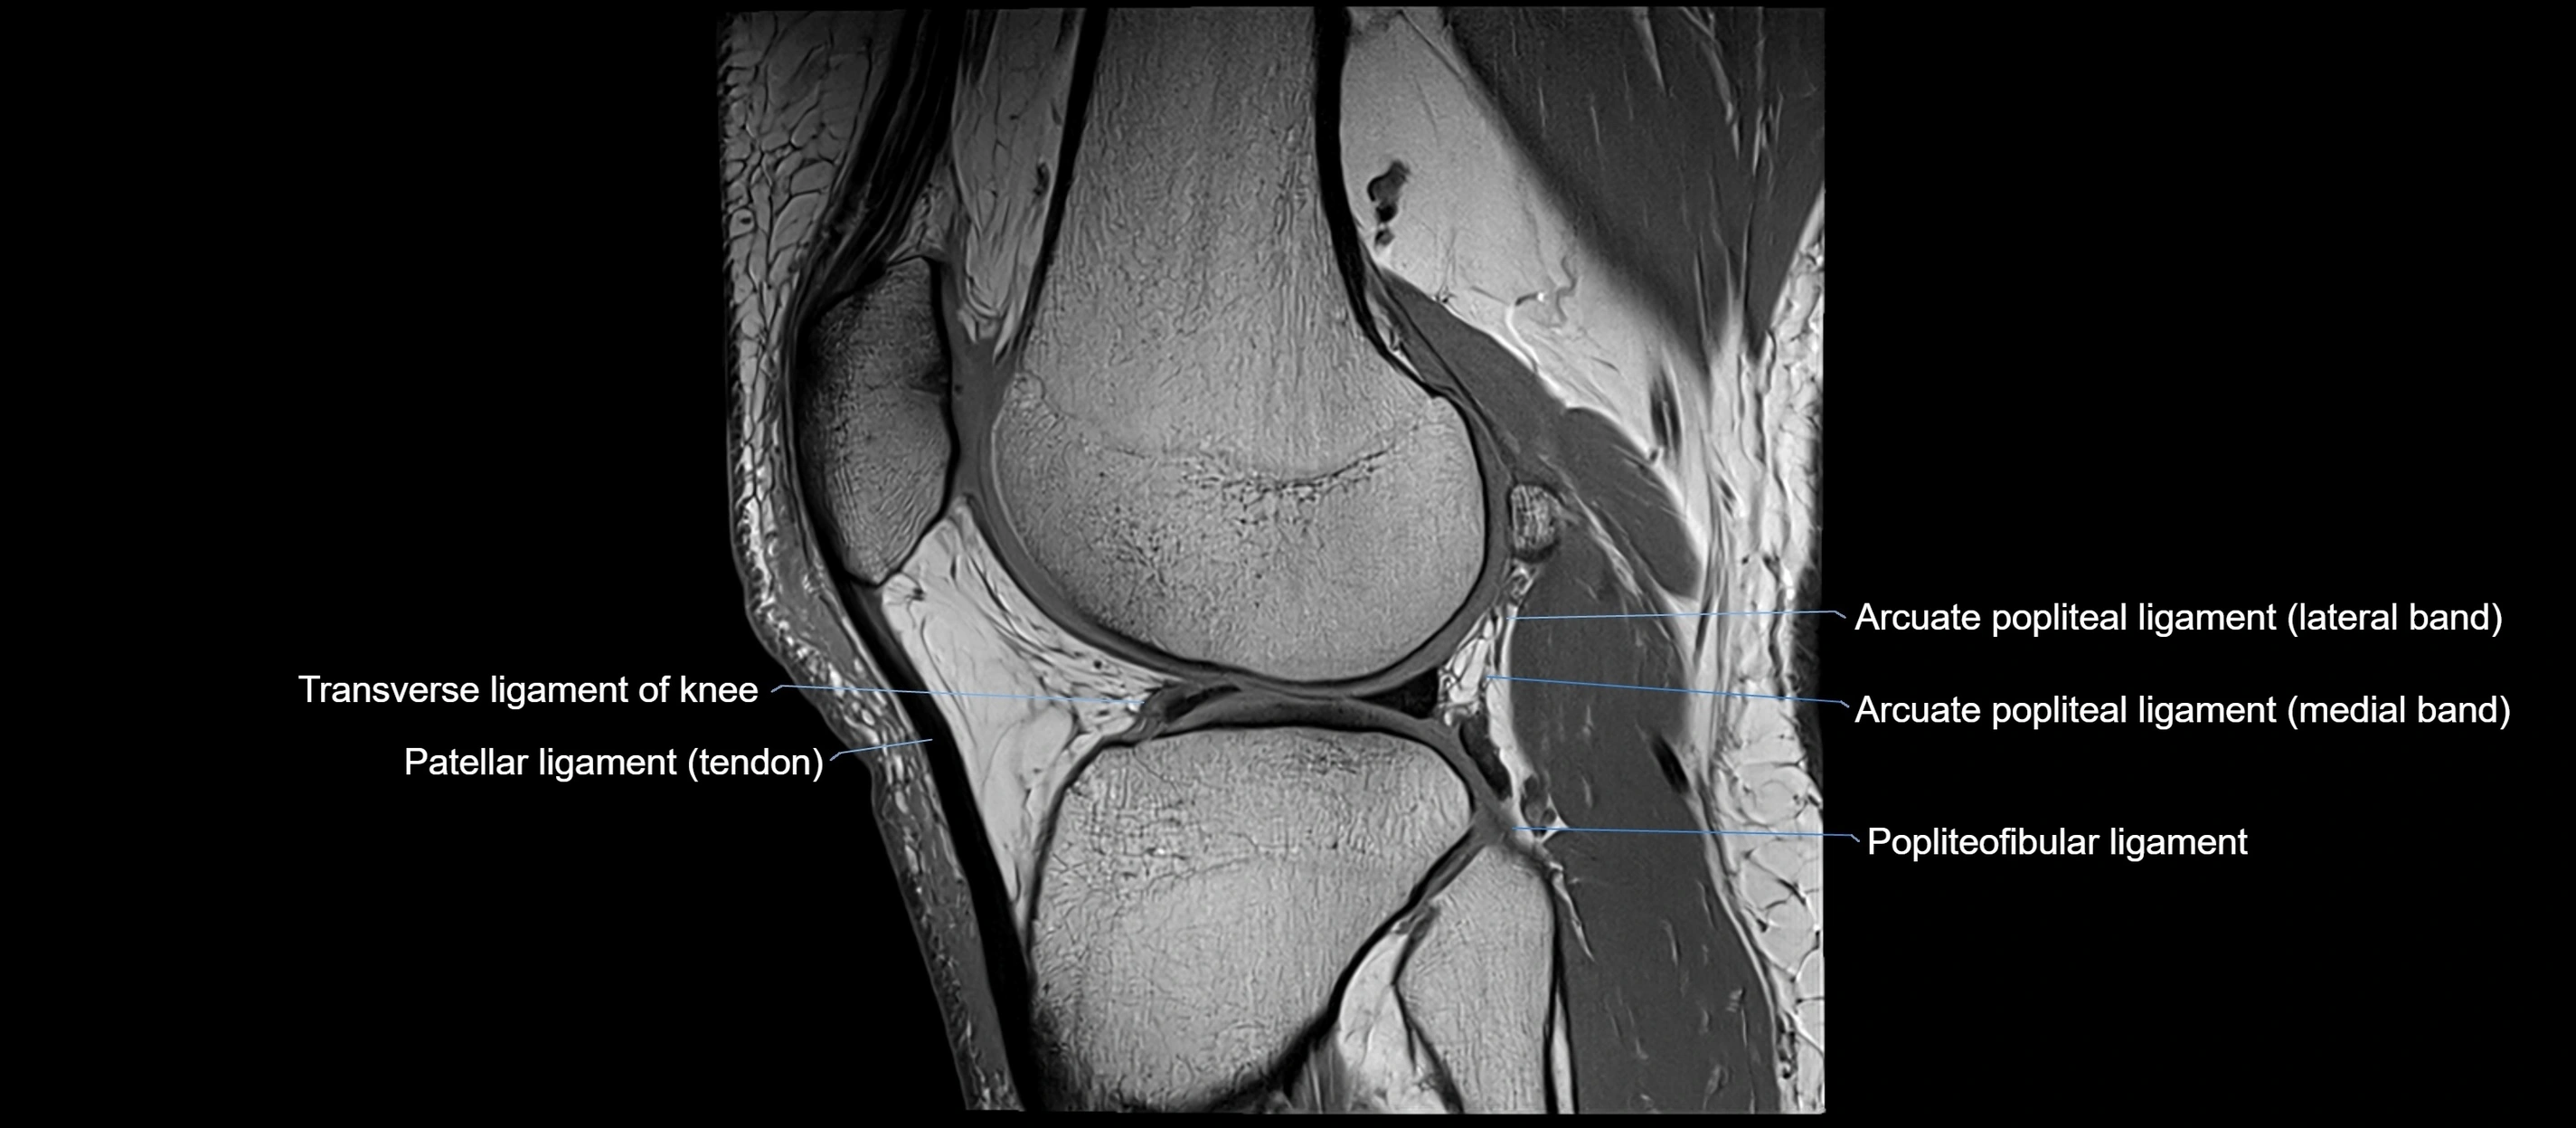

MRI images

image